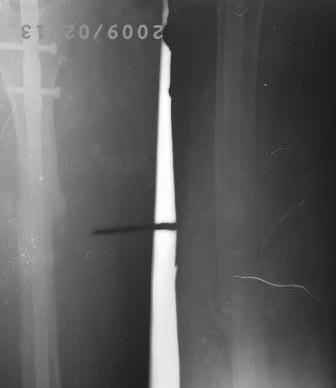

[Ortho] Искривление и/м штифта

12.02.09г б-ная оперирована: з/остеоклазия (без особого труда-

видимо тугой ложный сустав) коррекция деформации, удаление штифта

из надвертельной обл, рассверление канала гибкими развертками,

реостеосинтез блокируюшим гвоздем Д-11мм.

P.S. Снимки не качественные, извиняюсь! последний снимок ЭРГА, два снимка объединил.